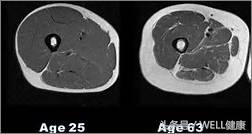

颈肩腰疼痛,多是因为深层肌肉退化,不能配合浅层肌肉工作,脊柱压力变大,不能维持关节稳定性,从而导致疼痛。

【深层肌肉退化对比图】

颈肩腰疼痛,不仅影响着我们的工作与生活,还会影响身体平衡力,导致体态不美观。